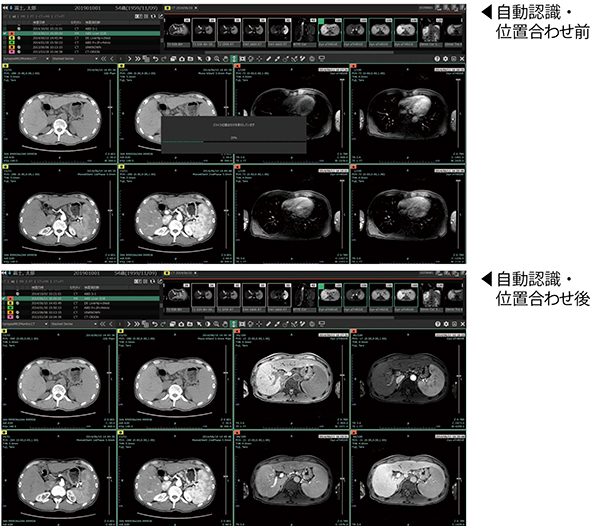

自動認識・位置合わせ機能

臓器セグメンテーション技術を生かした自動位置合わせ機能。同一モダリティだけではなく,CT,MRIなど異なるモダリティ間の位置合わせを行える。画面は肝臓の造影CT(左4シリーズ)を基準に,EOB-MRI(右4シリーズ)の位置合わせを行った例。

SAI viewerで臓器セグメンテーション技術が活用されているのが,過去画像との自動位置合わせ機能である。自動位置合わせでは,抽出された臓器の位置を相対的に照合して対応づけを行い,2つの画像の位置を合わせた状態で表示する。読影では,過去画像と比較して経時的な変化を確認するが,従来は読影医が目視でスライスを選択して手動で位置合わせを行っていた。SAI viewerでは,対象となる画像データを選択して開くだけで,スライス位置が自動で同期される。鈴木先任准教授は,「開いた瞬間から比較読影が始められます。今までと比べて1件あたり15秒程度は短縮されていると感じます」と述べる。菊地医師は,「一度SAI viewerで自動位置合わせを使って便利さを知ってしまうと,元には戻れません。まれにずれることがありますが,位置合わせの精度は高いと思います」と評価する。

同一モダリティの過去データだけでなく,CTとMRIなどの異なるモダリティでの位置合わせも可能だ。さらに,PETやSPECTなどの核医学検査とのフュージョン画像にも適応した機能は,核医学画像の読影に特化した表示を可能にした“核医学ビュー”(オプション)として提供されている。